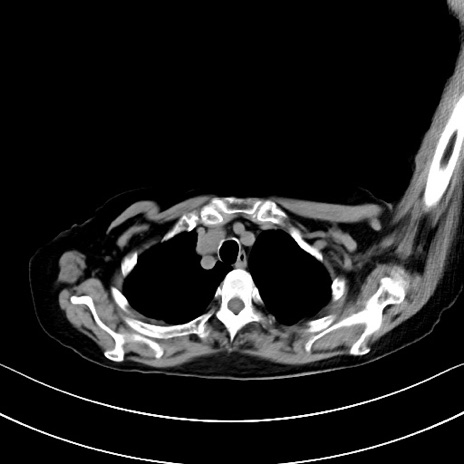

横断像

他院CT